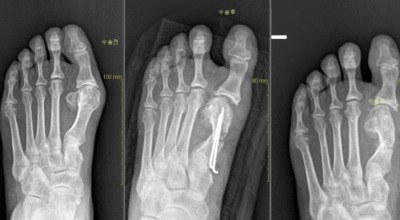

보존적 요법은 변형이 심하지 않은 경우 먼저 고려되는 치료법입니다. 굽이 높고 신발코가 뾰족한 신발은 피하고, 편안한 신발을 착용하여 발의 압박을 최소화합니다. 또한, 신발 안에 중족골 패드나 발가락 교정기 등 교정 도구를 사용하여 압력을 재분배하고 증상을 완화시킵니다. 만약 보존적 요법으로 증상이 완화되지 않거나 통증이 매우 심할 경우, 수술이 고려됩니다.

초기 단계에서는 건막류(두꺼운 혹)를 절제하는 건막류절제술을 시행합니다. 돌출된 건막류를 절제하여 각도를 교정하고, 짧아진 근육이나 연부조직을 늘려주는 비교적 간단한 수술입니다. 다른 발가락의 변형이 동반되거나 뼈의 과잉 성장이 심한 경우에는 뼈를 깎고 방향을 돌린 뒤 발가락이 똑바로 펴지도록 철사로 고정하는 교정절골술을 시행합니다. 양쪽 발이 모두 변형된 경우, 대개 한 번에 한쪽만 수술합니다.